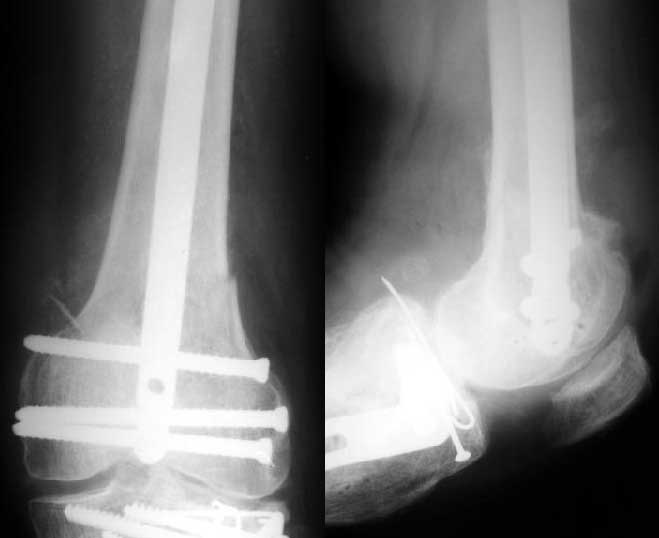

1

In the supracondylar nail system both the ends are lockable by jig and no free hand technique is needed.

Alex>> Than in the presented case?

I do not see the proximal bolts; I presume they must be at he trochanter level. In a supracondylar nail you are able to see both side bolts in one picture. ( Enclosure)